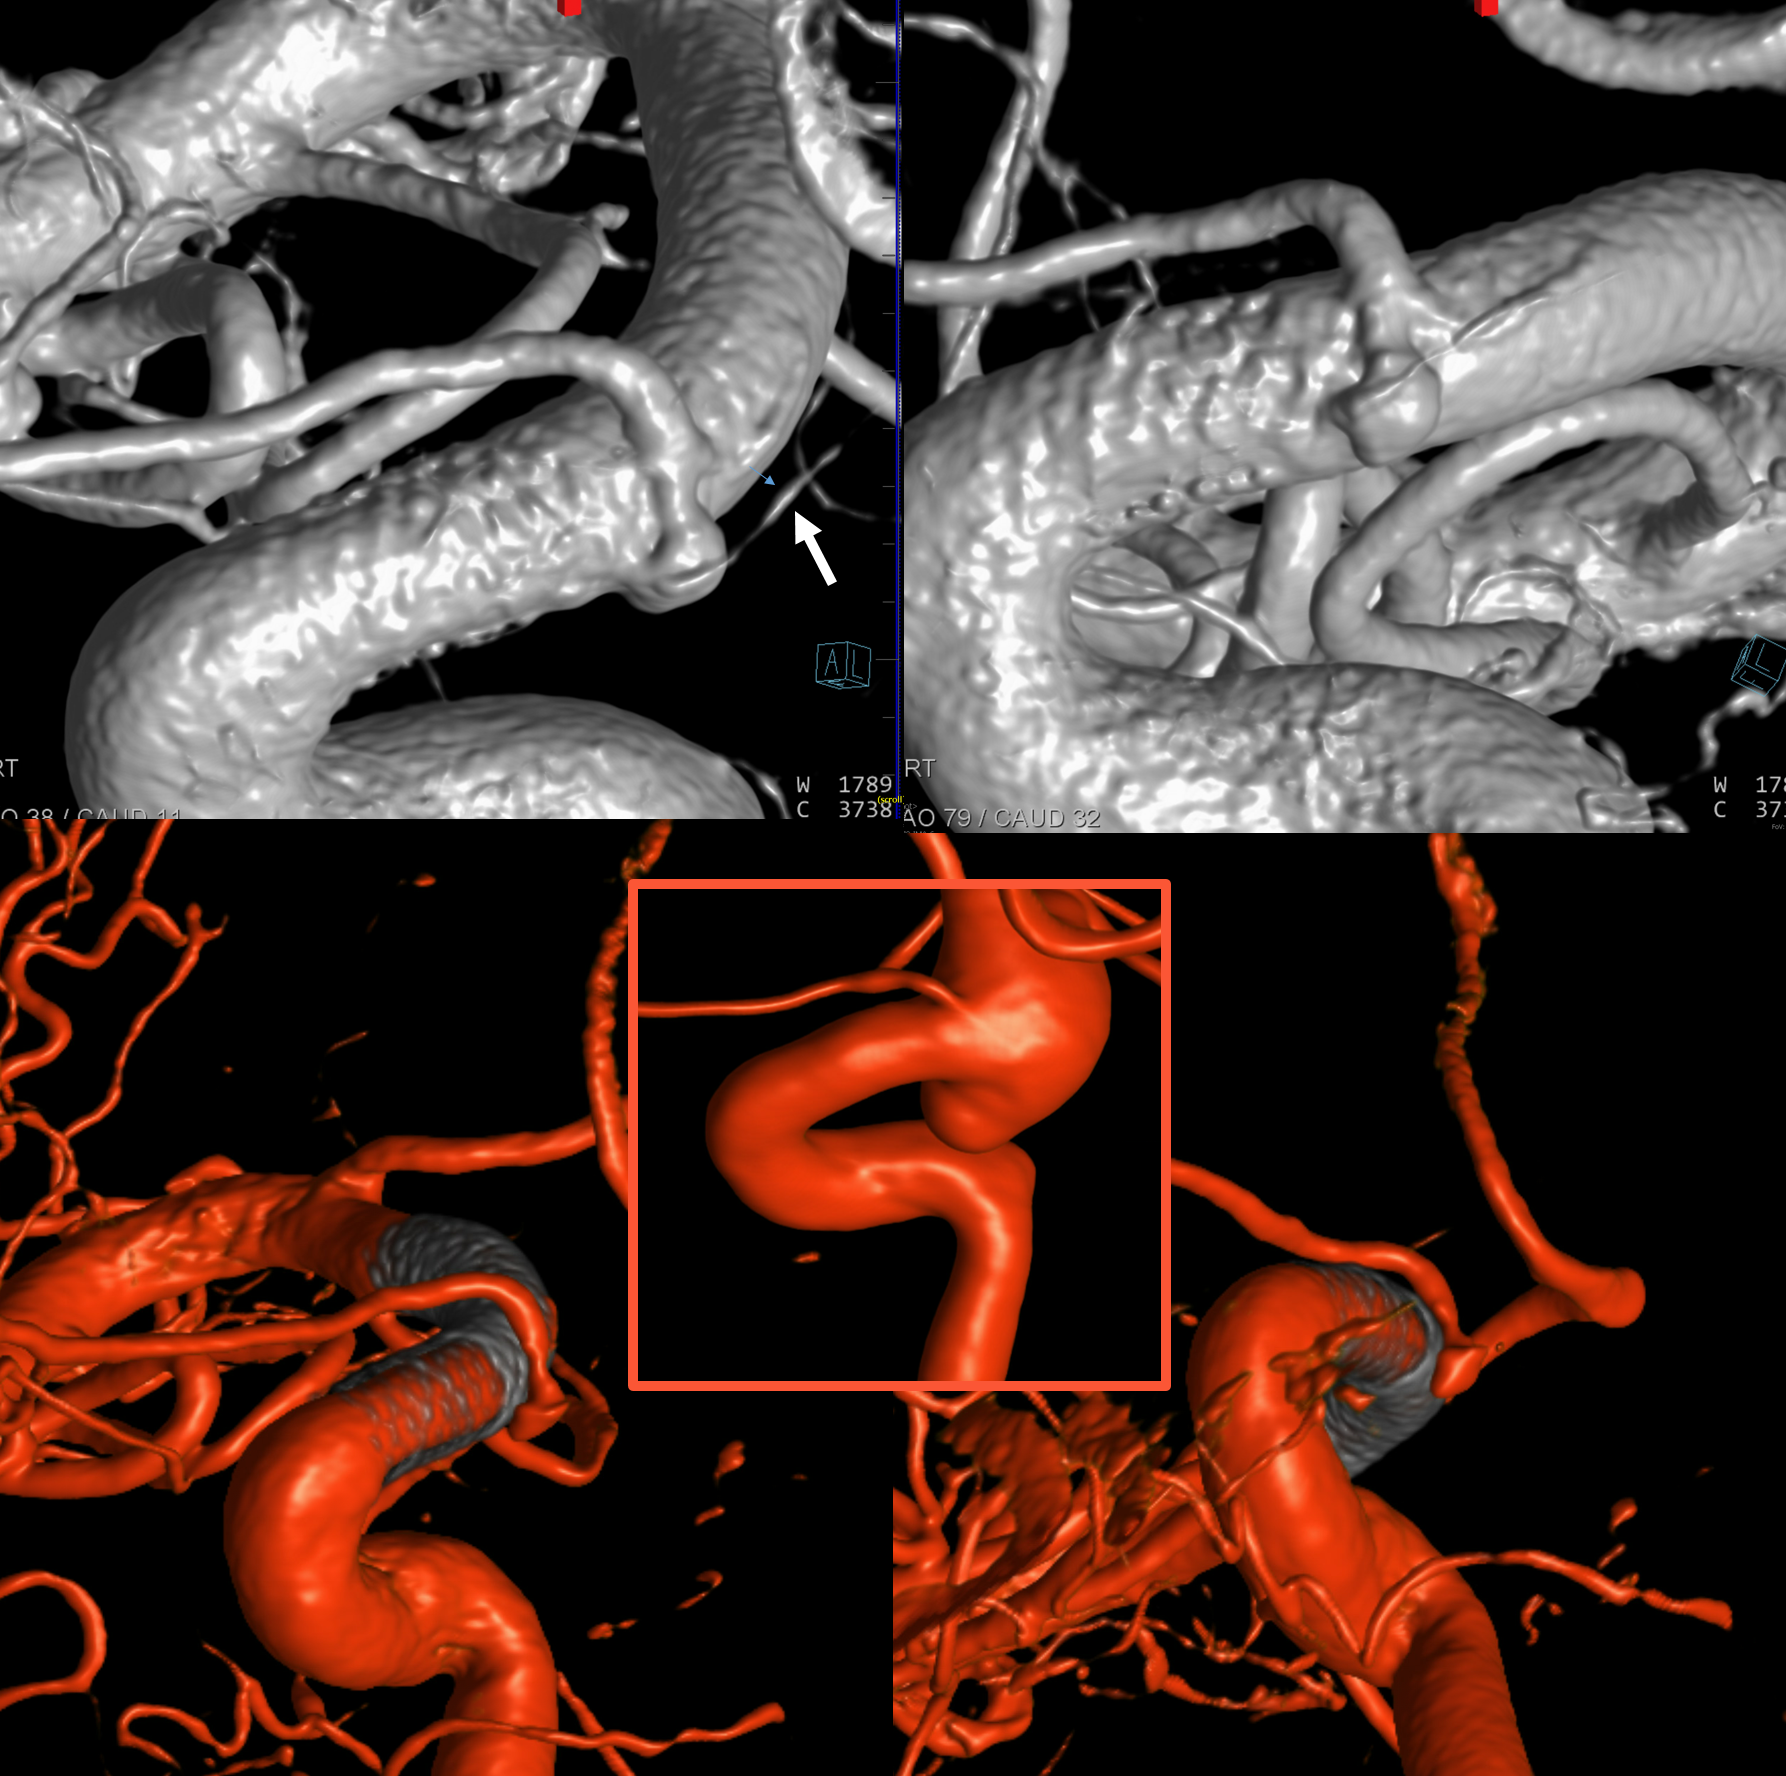

The patency of jailed vessels post technically optimal flow diversion (good wall apposition, good antiplatelet coverage) is principally determined by the collateral potential of the jailed artery. Ophthalmics occlude, asymptomatically in pretty much all cases, because of rich external collateral networks. One way to estimate collaterals is to see what happens to arteries post flow diversion. Below, pre-treatment top row shows two patent superior hypophyseals (arrows) and ophthalmic. Six months later (bottom row), the aneurysms and ophthalmic are closed, while superior hypophyseals remain patent.

Another Example

Note stenosis at the proximal segment of the device due to the proximal edge terminating on the curve of the anterior genu (dashed arrow). This is a kind of T-bone configuration which usually heals with a stenosis.

Patent Superior Hypophyseal artery (arrow) post Pipeline Embolization Device placement (6 months post).

Power of Cone Beam CT imaging

Even the smallest superior hypophyseal arteries can be seen with advanced cone beam CT. Top left is an already high resolution cone beam CT volume rendered image with no apparent Superior Hypophyseal. Windowing to increase sensitivity allows for visualization of a tiny superior hypophyseal (arrow) — top right image. Bottom row are axial (left) and coronal (right) MIP images, showing the same artery, as well as beautifully seen pituitary stalk (dashed arrow)